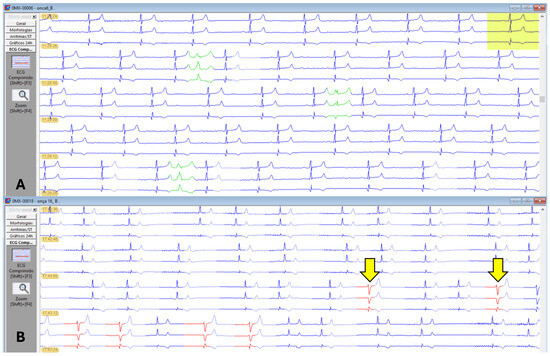

A second-degree atrioventricular block, Mobitz type II (Figure 4), was observed in six animals, one male and five females. Extrapolating the reference value used in dogs and animals in G1 and G4, as well as the overall average, showed a PR interval greater than 140 ms, indicating a first-degree atrioventricular block (Table 1).

Additionally, the average PR interval duration in animals from groups G1 and G4 exceeded 140 ms, characterizing first-degree atrioventricular block (AVB) compared with reference values in dogs [45]. Oliveira et al. [46] also observed first-degree AVB in pumas (Puma concolor) anesthetized with sevoflurane or isoflurane. Six animals in this study exhibited a second-degree atrioventricular block, Mobitz type II, possibly due to increased vagal tone induced by the drugs. Holter electrocardiography parameters rMSSD, pNN > 50%, SDNN, SDANN, and SDNNIDX suggest greater heart rate variability, indicating parasympathetic autonomic nervous system activity.

Figure 4. Electrocardiographic recording. Sinus rhythm with a heart rate of 62 beats per minute and second-degree atrioventricular block, Mobitz type II, gain n, and speed 50 ms. Note the presence of a non-conducted p wave (yellow line) in jaguars anesthetized with medetomidine and ketamine.